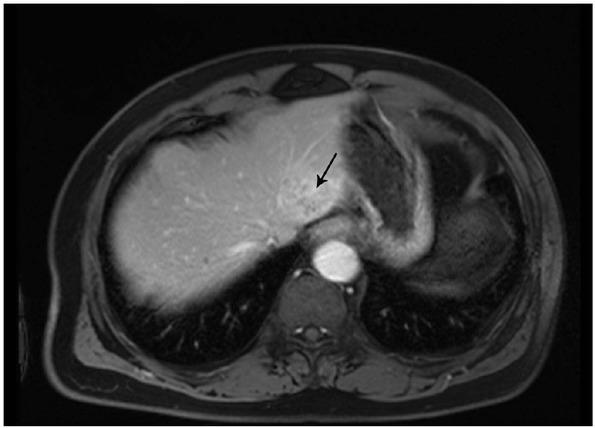

Hepatic epithelioid hemangioendothelioma (HEHE) is an extremely rare malignancy of vascular origin. When most patients with HEHE are diagnosed, they have a diffuse nodular phenotype, which is usually unresectable. A single nodular phenotype is found in only a small proportion (13%) of patients, and most are reported to be located in the right lobe of the liver. Although the prognosis of HEHE is considered more favorable than that of other hepatic malignant tumors, the 5-year survival rate is reported to be 64% after treatment. Herein, we present an unusual case of resectable HEHE of a single nodular type in the left lobe of the liver. The patient survived 15 years without recurrence after the multimodal treatment of radical resection and postoperative chemotherapy with thalidomide. The aim of the present study is to emphasize that multimodal treatment of radical resection followed by chemotherapy with thalidomide may achieve a relatively good survival outcome in patients with resectable HEHE of a single nodular type.

肝上皮样血管内皮瘤(HEHE)是一种极为罕见的血管源性恶性肿瘤。大多数HEHE患者确诊时具有弥漫性结节表型,通常无法切除。仅一小部分(13%)患者表现为单个结节表型,且多数报道位于肝右叶。尽管HEHE的预后被认为比其他肝脏恶性肿瘤更乐观,但据报道治疗后的5年生存率为64%。在此,我们报告一例罕见的可切除的肝左叶单结节型HEHE病例。该患者在接受根治性切除及沙利度胺术后化疗的多模式治疗后存活15年无复发。本研究的目的是强调对于可切除的单结节型HEHE患者,根治性切除后联合沙利度胺化疗的多模式治疗可能取得相对良好的生存结果。